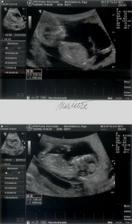

Vytoužené mimi . Vzhledem ke zdravotním problémům, operaci a věku mám za sebou IVF u Apolináře .Přes upozornění že napoprvé s tím raději nemáme počítat a šance že se uchytí obě není velká - čekáme dvojvaječná dvojčátka, která zatím ignorují tabulky a rostou stejně jako jedináčci. A vypadá to na kluka a holčičku. Děkuii všem u Apolináře a všem "snažilkám " za pomoc.